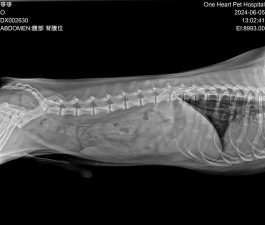

椎间盘疾病是一种导致脊髓和/或脊髓神经受压的脊柱退行性疾病。它是狗脊髓疾病的常见原因,尤其是小型犬,尤其是腊肠犬、比格犬、狮子犬、拉萨犬和北京犬。在这些品种中,椎间盘可能在生命的最初几个月开始退化。椎间盘突出或“滑脱”导致严重体征可能会在1至2岁时突然发生。相比之下,大型犬种的椎间盘退化通常发生在5岁以后,症状会慢慢恶化。椎间盘突出最常见于颈部和背部中部。颈部椎间盘突出会导致颈部疼痛、僵硬和肌肉痉挛。可能会出现肌肉无力或其他症状,从腿部轻度部分瘫痪到所有腿部完全瘫痪。背部中间的椎间盘突出会导致背部疼痛,可能还会导致脊柱弯曲和不愿移动。神经系统症状包括后肢运动控制丧失、瘫痪和尿失禁。在瘫痪的动物中,通过捏脚趾或尾巴并观察狗是否做出行为反应来确定是否存在疼痛感非常重要。

椎间盘突出的诊断需要x射线、脊髓造影、计算机断层扫描或磁共振成像。有轻微至中度症状但仍能感觉到疼痛的狗通常会在休息几周后康复。可以使用抗炎药或止痛药,但通常只有在狗可以在笼子里休息的情况下才能使用。如果狗增加活动,椎间盘可能会进一步挤压,加重脊髓压迫。不幸的是,30%至40%的病例会复发。对于有严重神经症状的狗,必须及时进行手术以缓解脊髓压力。如果药物治疗不成功并且症状复发,也需要手术。如果狗仍然能感觉到疼痛,手术后的恢复前景是好的。如果在痛感丧失后手术延迟超过24小时,恢复的机会就会减少。